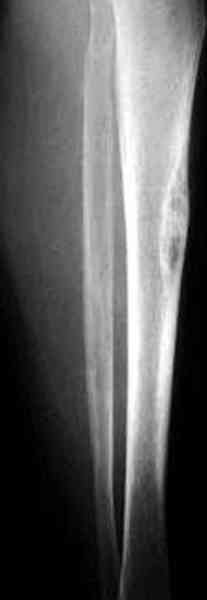

"При его рассмотрении с рентгенологом и морфологом сошлись, что это не фиброзная дисплазия, что было первым предположением по рентгенограммам. В полости было и мягкотканое образование. Окончательно заключение дадут через несколько дней"

По локализации и по характреру опухоли мало напоминает остеобластому, может, представленные биопсийные материалы адамантиномы помогут вашим морфологам дифференцировать опухоль (Basiloid cells, pseudoglandular pattern and peripheral palisading)

В литературе "A Classic Adamantinoma Arising from

Osteofibrous Displasialike Adamantinoma in the Lower Leg: A case report and Review of the Literature похожие снимки.